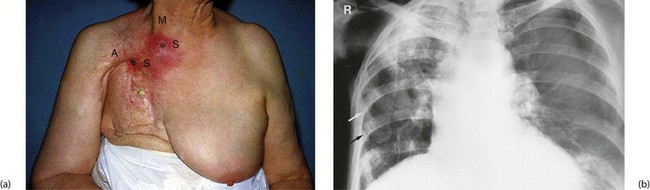

Radiotherapy is often valuable in providing symptomatic relief in advanced disease. In ulcerating breast cancer, radiotherapy can shrink the primary lesion, permitting healing of overlying skin. Similarly, the distressing symptoms of cough, haemoptysis and pleuritic pain from advanced lung cancer can be eased and symptoms of local recurrence can often be controlled, e.g. pain from rectal cancer. Indications for palliative radiotherapy are summarised in Box 13.4.

Modern radiotherapy using high-energy sources with meticulous treatment planning and delivery causes fewer side-effects than the orthovoltage treatment used in earlier days. Side-effects such as osteoradionecrosis are rare (see Fig. 13.1), but endarteritis obliterans may be a long-term complication affecting any tissue subjected to radiotherapy. The effect is progressive impairment of blood supply, loss of specialised tissues and replacement with fibrosis. In the chest, radiotherapy can cause pulmonary fibrosis and in women treated for left-sided breast cancer, there is an increased risk of cardiac events; techniques have been modified as a result. In the gastrointestinal tract, the effects of radiation on bowel (radiation enteritis) can be particularly serious, with continued bleeding (in large bowel) and stricture formation (in small bowel). The same reaction probably accounts for delayed or incomplete healing after surgery with breakdown of intestinal anastomoses or formation of internal fistulae. Radiation colitis most commonly results from treatment of uterine cervical cancer.